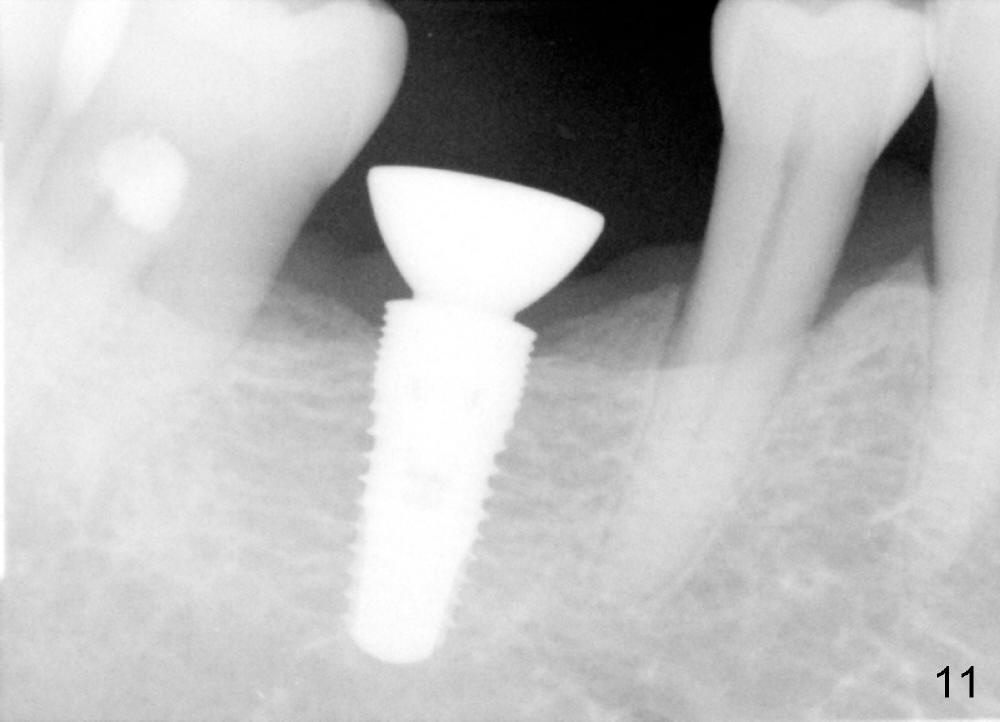

When a positioning pin is placed in the osteotomy with 10 mm deep, the sensor cannot be placed deep enough because of pin interference so no IAC is visible (Fig.4). When the pin is removed and the sensor is placed low enough, IAC is clearly shown, but the osteotomy is barely visible (Fig.5 pink dashed line). With information obtained from pre- (Fig.2,3) and intra- (Fig.4,5) op PA, twelve mm of osteotomy appears to be appropriate. A final implant (5.3x12 mm) is placed with separation from IAC (Fig.6, insertion torque 50 Ncm). A healing abutment is placed (Fig.7,8), which helps retain perio dressing (Fig.9). Two weeks later, the gingiva heals around the abutment (Fig.10). Four months postop, the implant appears to osteointegrate (Fig.11). A cemented abutment is placed (Fig.12). With supragingival margin, oral hygiene is easily maintained (Fig.13). Due to delayed placement, the gingival embrasure is extremely large (*). The issue is much less with immediate implant.